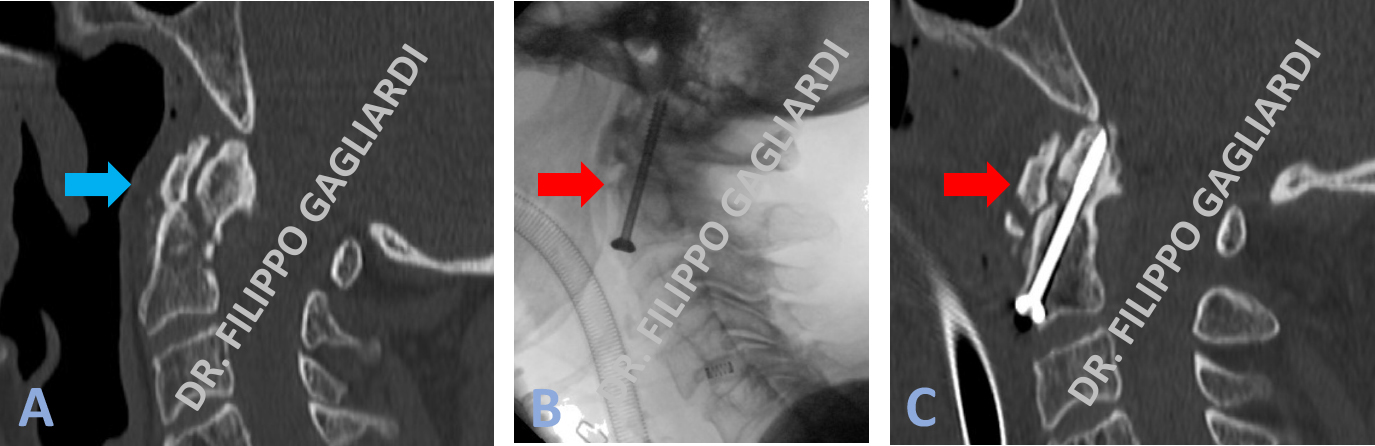

Caso di frattura del dente dell’epistrofeo (seconda vertebra cervicale) (frecce rosse in Figure A e B). Condizione a potenziale rischio di vita; la dislocazione del frammento potrebbe infatti determinare la compressione dei centri nervosi che regolano la respirazione. Il Paziente è stato sottoposto al posizionamento di due viti di riduzione della frattura. Si é proceduti con una tecnica definita “avvitamento del dente dell'epistrofeo per via anteriore”. Consiste nell’approcciare la colonna vertebrale cervicale dal davanti con una piccola incisione del collo passando quindi posteriormente alla faringe. Le viti hanno consentito di avvicinare i frammenti ed immobilizzarli in modo tale da consentirne la fusione e la formazione del callo osseo (frecce rosse in Figura C).

Stabilizzazione cervicale Caso di avvitamento per via anteriore del dente dell’epistrofeo (seconda vertebra cervicale) per una frattura con dislocazione del frammento all’interno del canale spinale contro il midollo spinale (Figura A). Immagine intraoperatoria (Figura B). Risultato post-operatorio (Figura C). Si vede la vite correttamente posizionata con la riduzione e la sintesi della frattura.